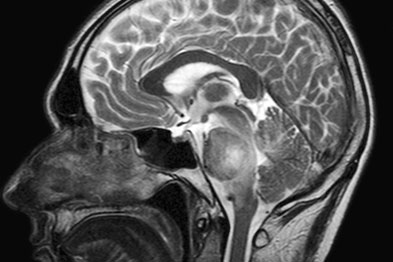

Internal Morphology Of The Brain In Slices And MRI

4-2 The rostral surface of a coronal section of brain through the level of the anterior commissureand the column of the fornix.The two MRI im-ages (both are inversion recovery) are at the same plane and show many ... Access Document